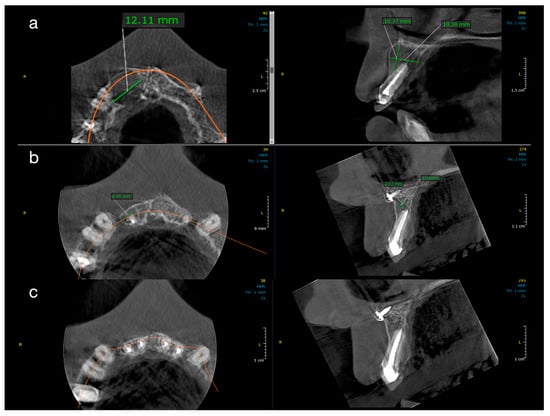

Figure 3. Sequential CBCT images of a case from Group 2 (decompression). Radiographic healing in a patient treated with root canal therapy and adjunctive decompression. (a) Baseline: critical-size lesion with dimensions of 12.11 mm (MD), 10.37 mm (BL), and 10.38 mm (V). (b) At 1 year: significant size reduction to 4.45 mm (MD), 3.67 mm (BL), and 3.84 mm (V). (c) At 2 years: residual lesion measuring ~3.67 mm in height and ~3.5 mm in width.

Figure 2 and Figure 3 illustrate representative cases from each group, highlighting the volumetric healing over time. In a Group 1 case (conventional treatment only), the initial lesion (~8–10 mm in diameter in each dimension) showed substantial shrinkage by the 1-year follow-up and almost complete radiological resolution by 2 years. By contrast, a Group 2 case (with decompression), which began with a larger cystic lesion (over 12 mm in its greatest dimension), demonstrated a dramatic reduction in lesion size after 12 months of decompression and continued healing at 24 months, leaving only a small residual radiolucency. These examples underscore the progressive radiographic healing observed in both treatment protocols.

All ten treated teeth remained asymptomatic throughout the follow-up, and sequential CBCT evaluations confirmed continuous lesion regression in every case. Table 1 and Table 2 detail the lesion size measurements (in mm) for each patient at baseline, 1 year, and 2 years in Group 1 and Group 2, respectively. Many lesions exhibited complete or near-complete radiological healing by the end of the observation period (recorded as 0.00 mm lesion diameter in at least one dimension for several cases in both groups). At baseline, Group 2 lesions were notably larger than those in Group 1. The mean initial lesion diameter in Group 2 was 13.7 mm (±3.34), compared to 7.3 mm (±1.74) in Group 1 (Table 3). This difference was statistically significant (p < 0.001), confirming that Group 2 started with more extensive periapical lesions. It is noteworthy that the baseline lesion size data in both groups showed no significant departures from normal distribution (see Table 4 for normality test results), which validated the use of parametric statistical comparisons.

By the 12-month follow-up, the lesion dimensions had decreased markedly in both groups (Table 3). In Group 1 (standard endodontic therapy), the mean lesion diameter reduced from 7.3 mm at baseline to 2.93 mm (±0.75) at one year. In Group 2 (endodontic therapy + decompression), the mean lesion diameter decreased from 13.7 mm to 5.21 mm (±4.75) at one year. Although the lesions in Group 2 remained larger in absolute terms after 12 months, the difference between the two groups was no longer statistically significant (p = 0.087). Figure 4 presents violin plots of the lesion size distributions at baseline and one year, illustrating the substantial shift toward smaller lesion diameters in both cohorts. The spread of the violin plot for Group 2 at one year was broader, reflecting greater variability in healing outcomes among those larger initial lesions. By the 24-month follow-up, both groups showed further improvement. Group 1 lesions had a mean diameter of 1.12 mm (±0.98), and Group 2 lesions averaged 2.41 mm (±5.15). This slight residual difference was not statistically significant (p = 0.356). Radiographically, most lesions in both groups had resolved or nearly resolved by two years, with only very small radiolucencies, if any, remaining. It was observed that Group 2 continued to exhibit a higher variability in lesion size outcomes at 24 months (as evidenced by a larger standard deviation and wider confidence interval in Table 3). Importantly, within each group, the reduction in lesion size from baseline was highly significant. Both Group 1 and Group 2 demonstrated statistically significant lesion shrinkage at the 1-year and 2-year evaluations compared to baseline (intragroup comparisons, p < 0.001 for all). This confirms that both treatment approaches achieved effective and progressive lesion resolution over time in their respective groups.